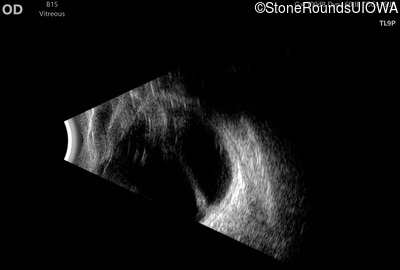

B-Scan Ultrasonography - Left - 20/300

Exemplar